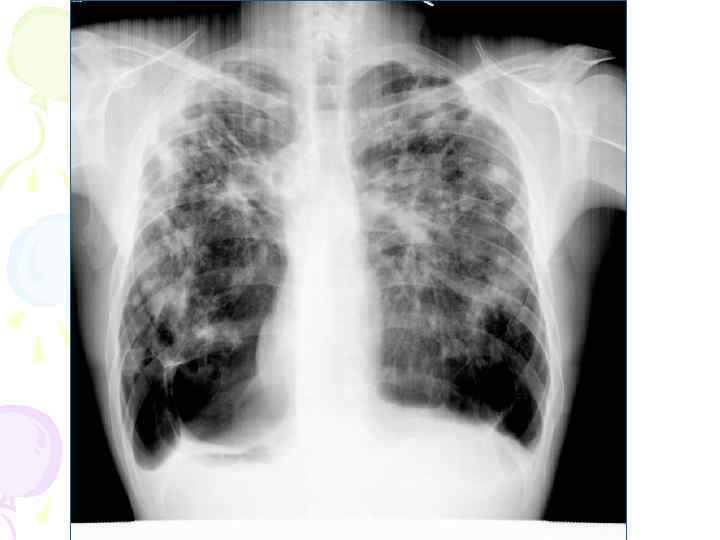

Рентгенологическая картина • множественные крупные / до 10 мм/ однотипные очаги преимущественно в верхних и средних отделах легких • Очаги округлой формы, малой и средней интенсивности, контуры нечеткие, часто расположены в виде цепочки вдоль продольных сосудов • Сливаясь, очаги образуют фокусы затемнения с участками просветления (распад) • При распаде в нескольких отдельных очагах формируются кольцевидные тени – штампованные каверны • При лимфогенной диссеминации очаговые тени с одной стороны, в средних и нижних отделах на фоне лимфангита, в корне кальцинаты

Хронический диссеминированный туберкулез патоморфология • Связан с повторными лимфогематогенными диссеминациями. Новые волны обострений приводят к новым свежим высыпаниям на фоне уже имеющихся изменений. Как правило процесс спускается сверху-вниз. • Часты поражения плевры, а также других органов в результате повторных волн гематогенной диссеминации (гортань, почки, кости и суставы, гениталии…) • Гипертензия малого круга кровообращения приводит к гипертрофии правого желудочка и легочному сердцу.

Рентгенологическая картина • Наблюдается полиморфная картина: очаги различной величины, формы и интенситвности, свежие и старые на фоне фиброзных изменений, больше в верхних отделах • Тенденции к слиянию очагов нет • Нарушается симметричность поражения • Могут наблюдаться как тонко- так и толстостенные каверны • Верхушки - интерстициальный фиброз, уменьшение объема, плевральные наложения, в нижних отделах - викарная эмфизема. С-м плакучей ивы. • Тень сердца сужена, имеет срединное положение (капельное сердце) • Фиброз и эмфизема обуславливают деформацию бронхиального дерева, что способствует развитию бронхоэктазов